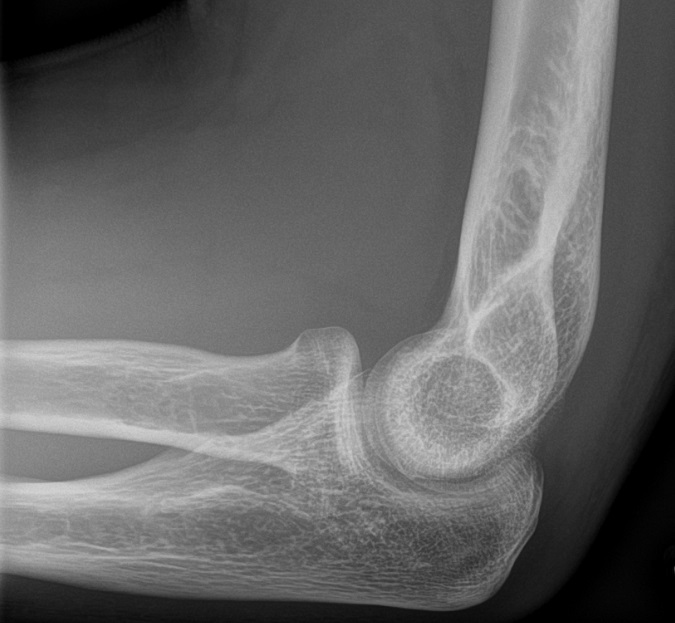

Normal sidobild (vuxet skelett)

Fettkuddar anteriort och posteriort om distala humerus, antyder fraktur (vuxet skelett)